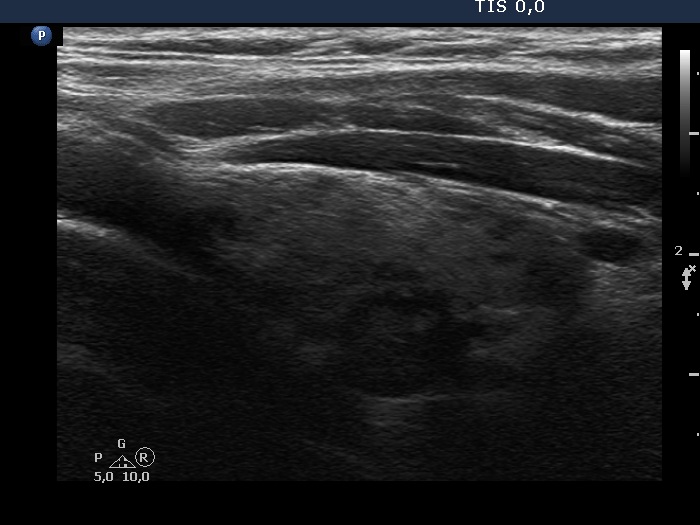

Second examination 2 years later (2nd row of images)

Clinical presentation. The patient had no complaints. The endocrinologist colleague noticed a significant increase in the size of the nodule on repeat ultrasound and he sent the patient for a repeat FNA.

Palpation: no abnormality.

Ultrasonography. The pattern was essentially the same. The only difference concerned the lesion in the dorsal part of the right lobe which clearly increased in size. Moreover, it became more obvious that the lesion had microcalcifications.

Aspiration cytology of the lesion resulted in Hashimoto's thyroiditis.

Suggestion: In agreement with the referring physician, surgery was proposed because there was a suspicion of thyroid cancer despite the negative cytology.

Histopathology disclosed Warthin-like variant of papillary cancer. and Hashimoto's thyroiditis.